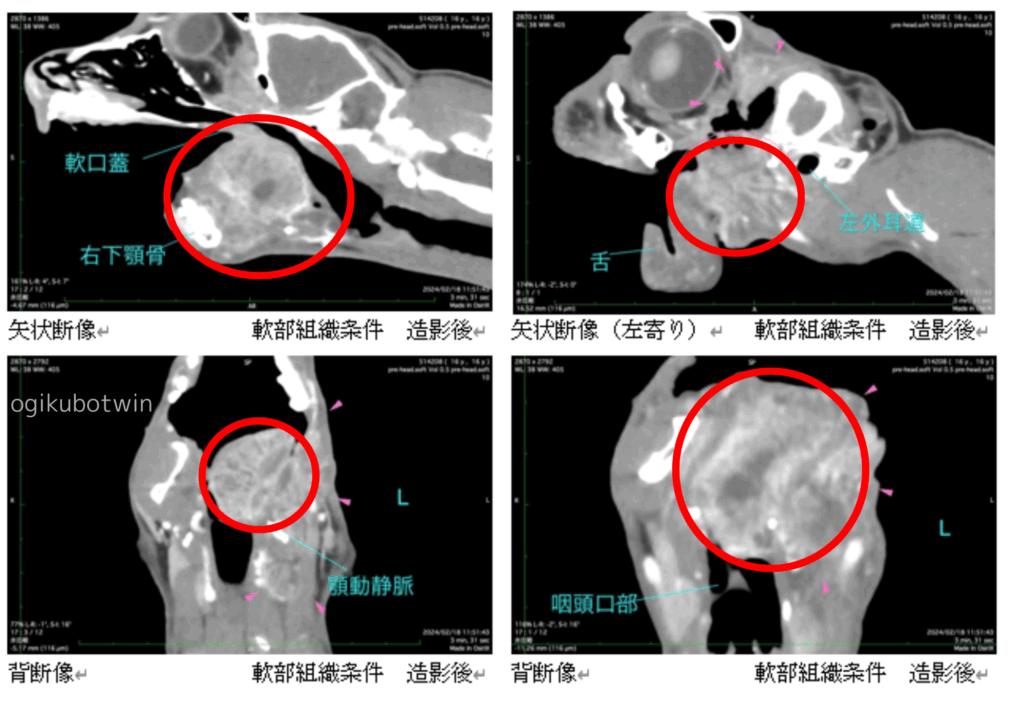

CT検査をしたところ、舌、脳、左眼窩への転移が疑われました。(赤丸の部分)